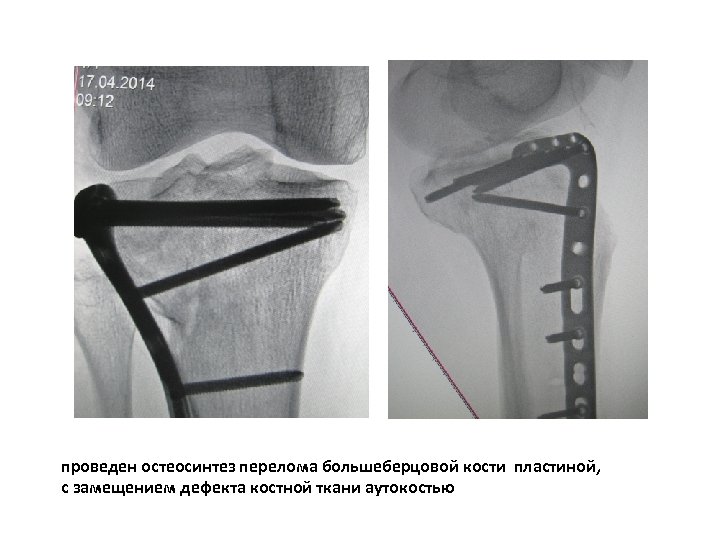

больной З. 54 года, получил оскольчатый, внутрисуставной перелом наружного мыщелка большеберцовой кости со смещением отломков, дефектом костной ткани

проведен остеосинтез перелома большеберцовой кости пластиной, с замещением дефекта костной ткани аутокостью